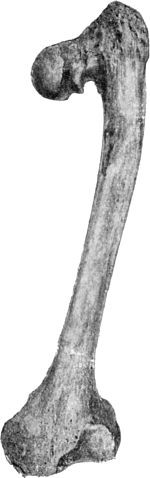

225 120.Upper End of Femur in advanced Arthritis Deformans of Hip

226 121.Femur in advanced Arthritis Deformans of Hip and Knee Joints

227 122.Tuberculous Synovial Membrane of Knee